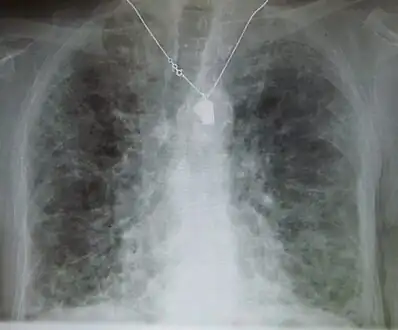

Pneumocystis pneumonia can present with interstitial lung disease, as seen in the reticular markings on this AP chest x-ray.

-